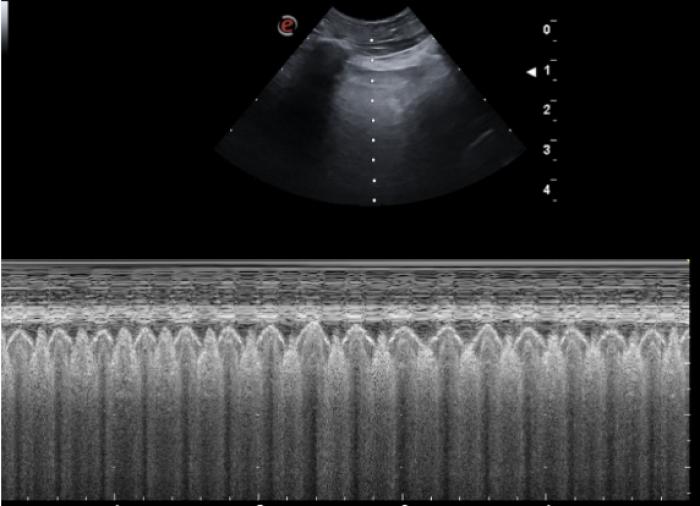

Comenzaremos posicionando el transductor perpendicular a las costillas en uno de los espacios intercostales, pudiendo evaluar al menos el espacio entre dos costillas, la línea PP y no más de 2-3 cm de profundidad de campo (Figura 1A-B).

Líneas A

Son las líneas hiperecogénicas, horizontales, paralelas a la LP y equidistantes (su separación es la misma que existe entre la piel y la superficie pleural) que se van extendiendo hasta el fondo del campo ecográfico. Son fruto del reflejo del ultrasonido en el aire pulmonar, volviendo este a la sonda y creando la repetición de dicha superficie (reverberación).

Son visibles en todo pulmón bien ventilado, pero también estarán presentes en el neumotórax por lo que en este punto es vital observar el deslizamiento de la LP para su diferenciación (Figura 3A-B).